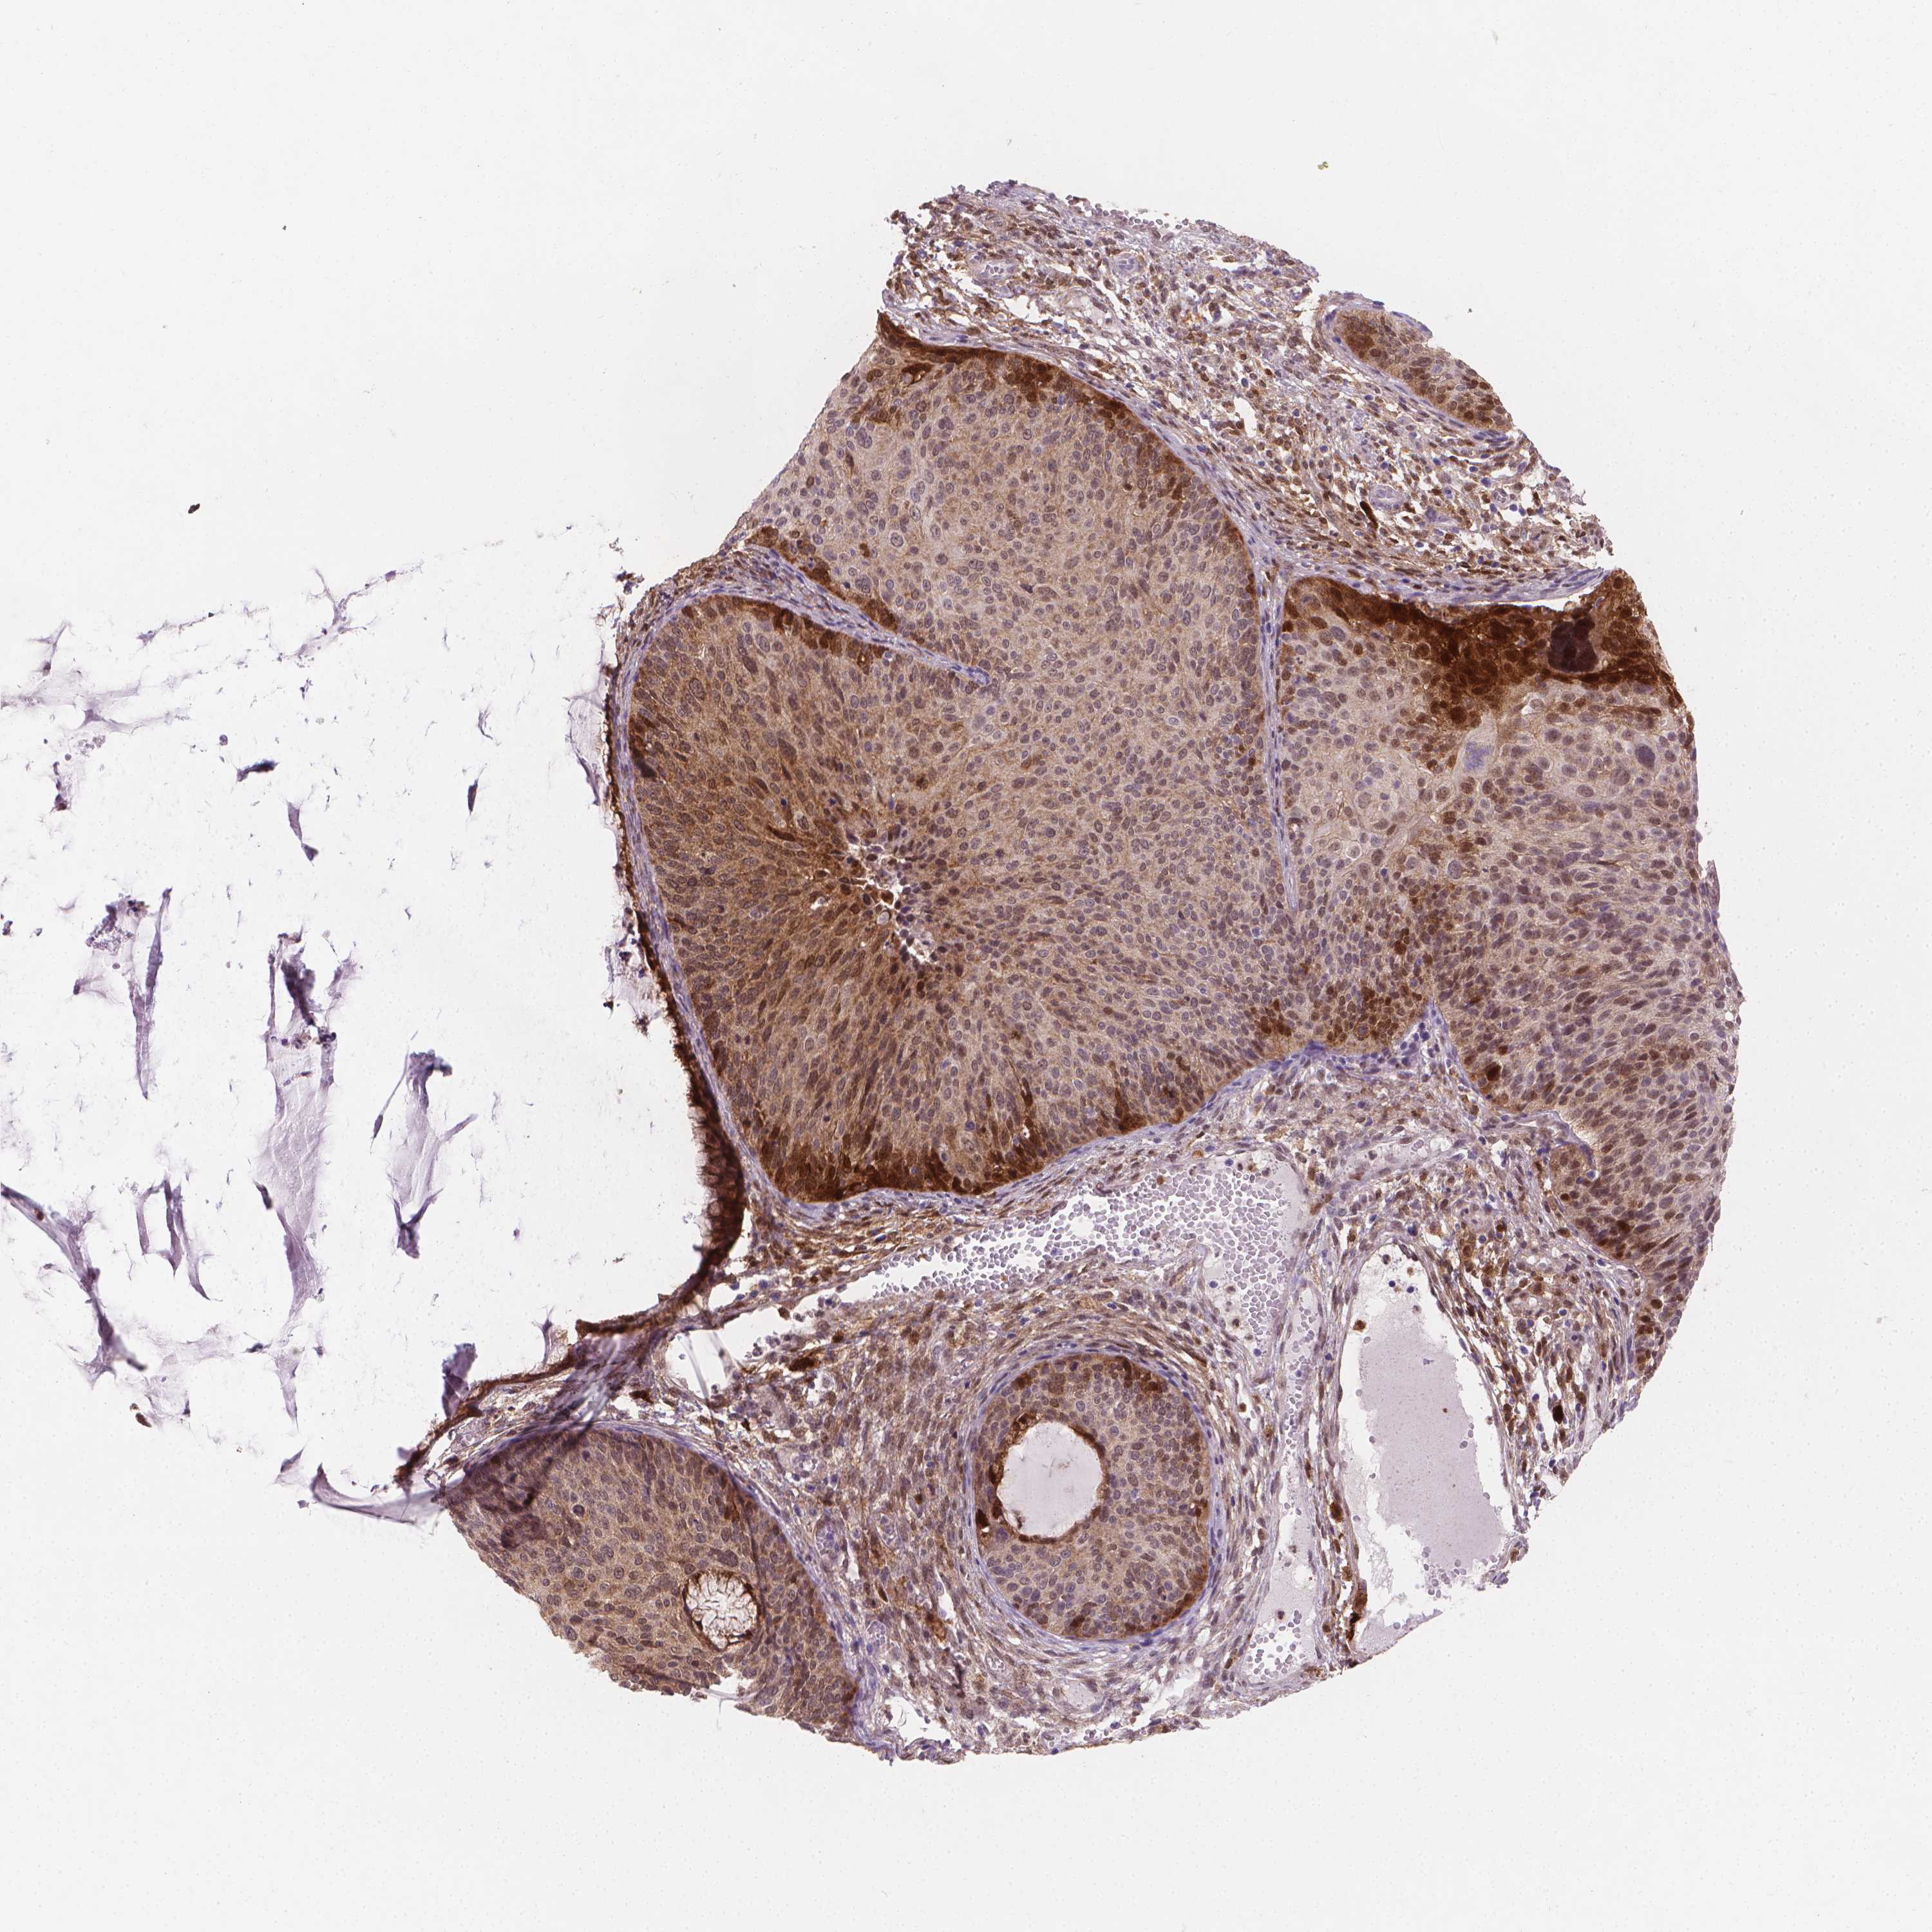

CERVICAL CANCER - Protein expressioni

A mouse-over function shows sample information and annotation data. Click on an image to view it in a full screen mode. Samples can be filtered based on level of antibody staining by selecting one or several of the following categories: high, medium, low and not detected. The assay and annotation is described here.

Note that samples used for immunohistochemistry by the Human Protein Atlas do not correspond to samples in the TCGA dataset.

Antibody stainingi

Antibody staining in the annotated cell types in the current human tissue is reported as not detected, low, medium, or high, based on conventional immunohistochemistry profiling in selected tissues. This score is based on the combination of the staining intensity and fraction of stained cells.

Each image is clickable and will lead to virtual microscopy that enables deeper exploration of all samples and also displays staining intensity scores, fraction scores and subcellular localization as well as patient and tissue information for each sample.

Antibody CAB004598

Staining

High

Medium

Low

Not detected

Intensity

Strong

Moderate

Weak

Negative

Quantity

>75%

75%-25%

<25%

None

Location

Nuclear

Cytoplasmic/membranous

Cytoplasmic/membranous,nuclear

Squamous cell carcinoma, NOS

Adenocarcinoma, NOS